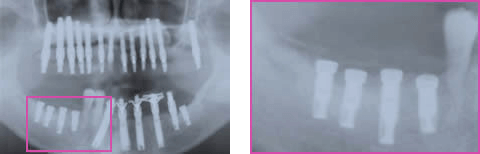

術後13週時のパノラマX線写真では予定した骨高径が得られており、移植骨と母床骨との境界は不明瞭でした(図8)。術後24週時のX線所見では予定した骨高径が得られており(図9)、翌週に同部にインプラントを4本埋入、造成した骨には豊富な血流が認められ、骨質は比較的硬く初期固定は十分に得られました(図10)。インプラント埋入後3ヶ月時にはオステオインテグレーションの獲得を確認し、現在プロビジョナルレストレーションにて機能負荷を開始しているが経過は良好です(図11)。

図9:下顎右側臼歯部 再GBR後 6M

超音波治療応用後

図10:下顎右側臼歯部 再GBR後 6M.1w

超音波治療応用後

二次手術

アバットメント装着

印象

図11:プロビジョナル レストレーション装置

荷重開始時(二次手術後5日)